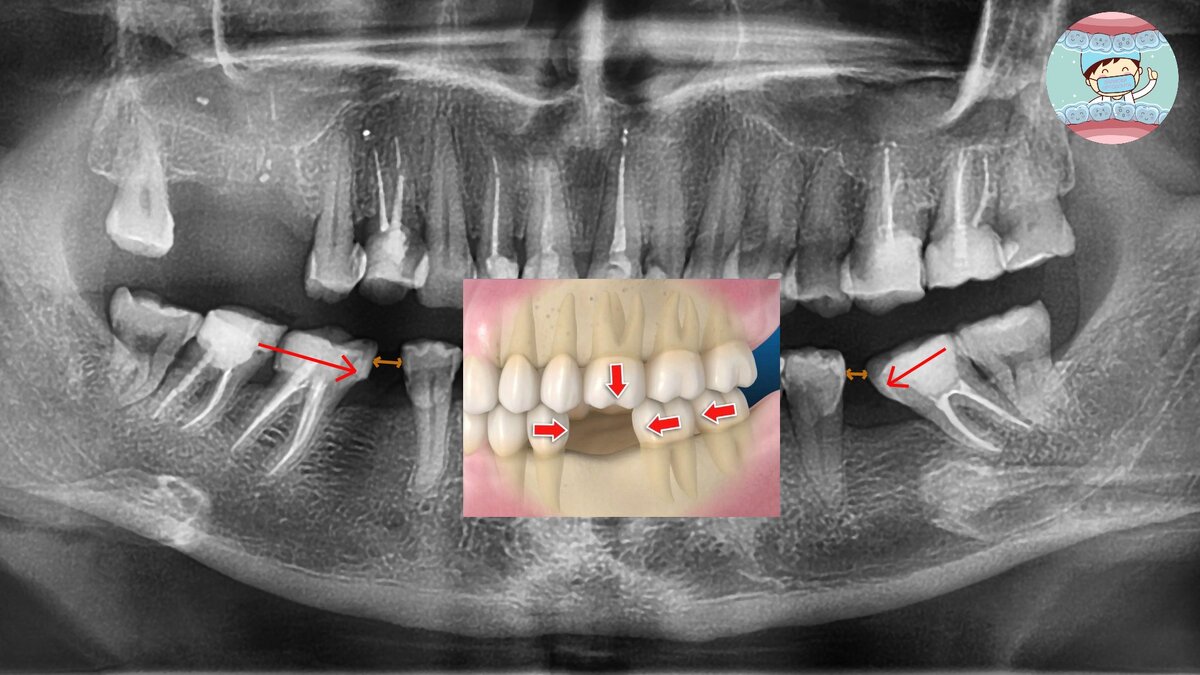

Разберем это на примере снимка конкретного пациента. 10 лет назад были удалены нижние большие коренные зубы. Его соседи сместились в сторону отсутствующего зуба.

Красными стрелочками показано, в каком направлении смещаются зубы, а коричневыми - насколько мало места осталось между зубами. К сожалению, коронка туда не поместится.